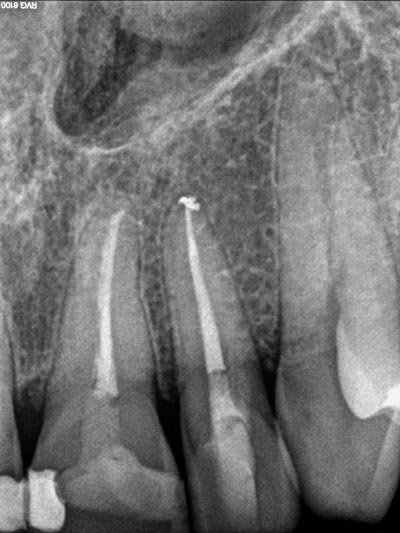

Imágenes: Reendodoncia en un molar inferior derecho

Imágenes: Radiografía de un ápice radicular en un incisivo central inmaduro tras trauma y necrosis pulpar de larga evolución. Se procedió al sellado radicular mediante apicorformación.